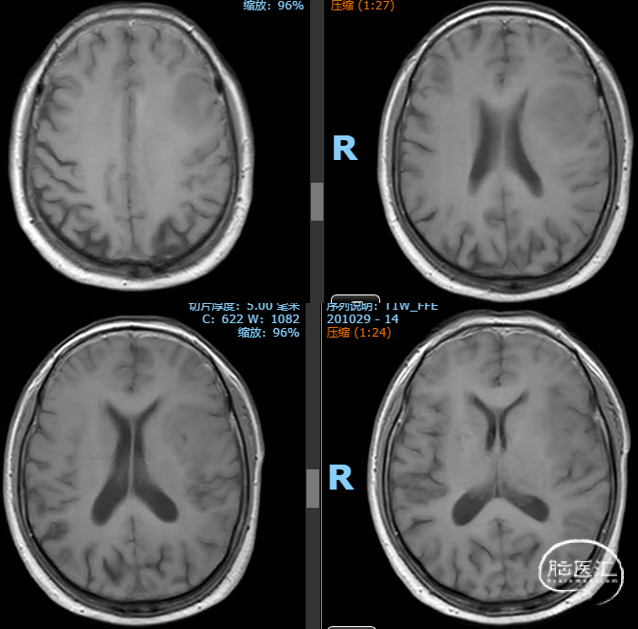

术后MR